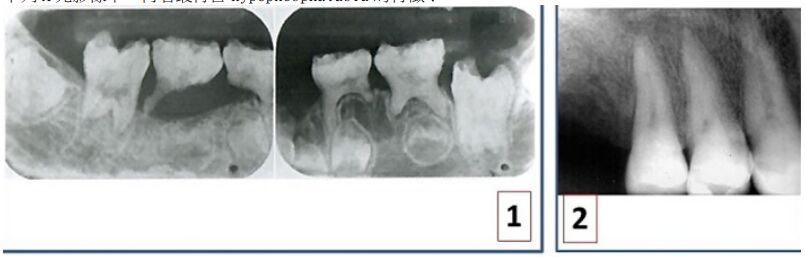

71.下列 X 光影像中,何者最符合 hypophosphatasia 的特徵?

(A)1 (B)2 (C)3 (D)4